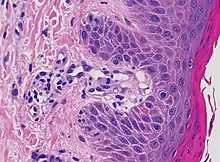

Additional testing may aid diagnosis. A skin biopsy may be taken to determine capillaritis of dermal vessels.[8] Capillaritis or pigmented purpura is skin condition that has brown-reddish patches on the skin, which is caused by leaky capillaries.[9] Such skin biopsies are sent to a laboratory for a pathological examination, where each biopsy is observed under a microscope.[3] A dermatologist may also perform a dermatoscopy.[3]